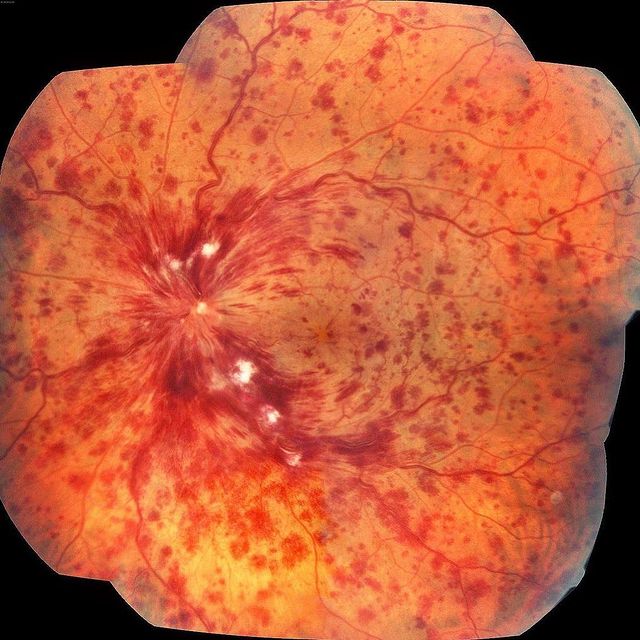

Окклюзия центральной вены сетчатки — это полное нарушение ее проходимости, при этом наблюдаются диффузные кровоизлияния во всех квадрантах сетчатки, расширение и извитость вен, ватообразные очаги, отек диска зрительного нерва, образование оптикоцилиарних шунтов на диске, неоваскуляризация диска, радужки и сетчатки. Жалобы на одностороннюю потерю зрения (не сопровождающуюся болью).

- Ишемический тип — множественные ватообразные очаги, обширное кровоизлияние в сетчатку, при флуоресцентной ангиографии обнаруживают обширную зону отсутствия капиллярной перфузии. Острота зрения снижается до 0,1 или меньше.

При офтальмоскопии обращают на себя внимание интраретинальные полиморфные сливные кровоизлияния, преимущественно располагающиеся в заднем полюсе. Значительное количество геморрагии формируется в поверхностных слоях сетчатки, имея форму пламени, подчеркивают ход нервных волокон. Если кровоизлияния находятся непосредственно под внутренней пограничной мембраной, то они прикрывают не только подлежащую сетчатку, но и ретинальные сосуды. Обширные кровоизлияния могут прорывать внутреннюю пограничную мембрану, тогда появляются преретинальные или интравитреальные геморрагии. Множественные точечные кровоизлияния указывают на поражение глубоких слоев сетчатки. Мелкие геморрагии могут быть единичными и располагаться изолированно, но чаще они группируются вокруг венул.

Все венозные сосуды переполнены темной кровью, расширены, извиты, в то же время артериолы сужены. Ретинальный отек наиболее выражен в заднем полюсе, причем участки отечной сетчатки могут прикрывать сосуды. Длительное существование отека сетчатки, особенно в области желтого пятна, в конечном счете, приводит к его постоянным структурным изменениям. При ишемическом типе тромбоза также часто офтальмоскопируется значительное количество мягкого экссудата. Диск отечен, границы его стушеваны или не определяются, перипапиллярная сетчатка также отечна. Физиологическая экскавация на диске не определяется, так как заполнена отечной тканью, венный пульс отсутствует. Нередко на отечном диске с расширенными капиллярами локализуются кровоизлияния, которые переходят и на окружающую сетчатку. Следует заметить, что ретинальные микроаневризмы, как правило, обнаруживаются не сразу, а по истечении острого периода тромбоза.